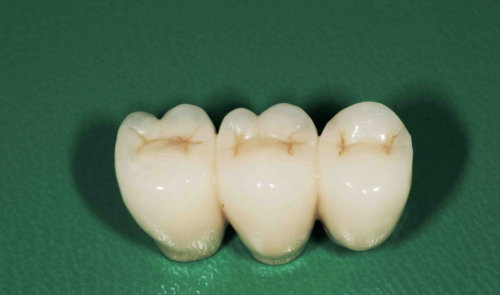

mit Kronen versorgte Implantate